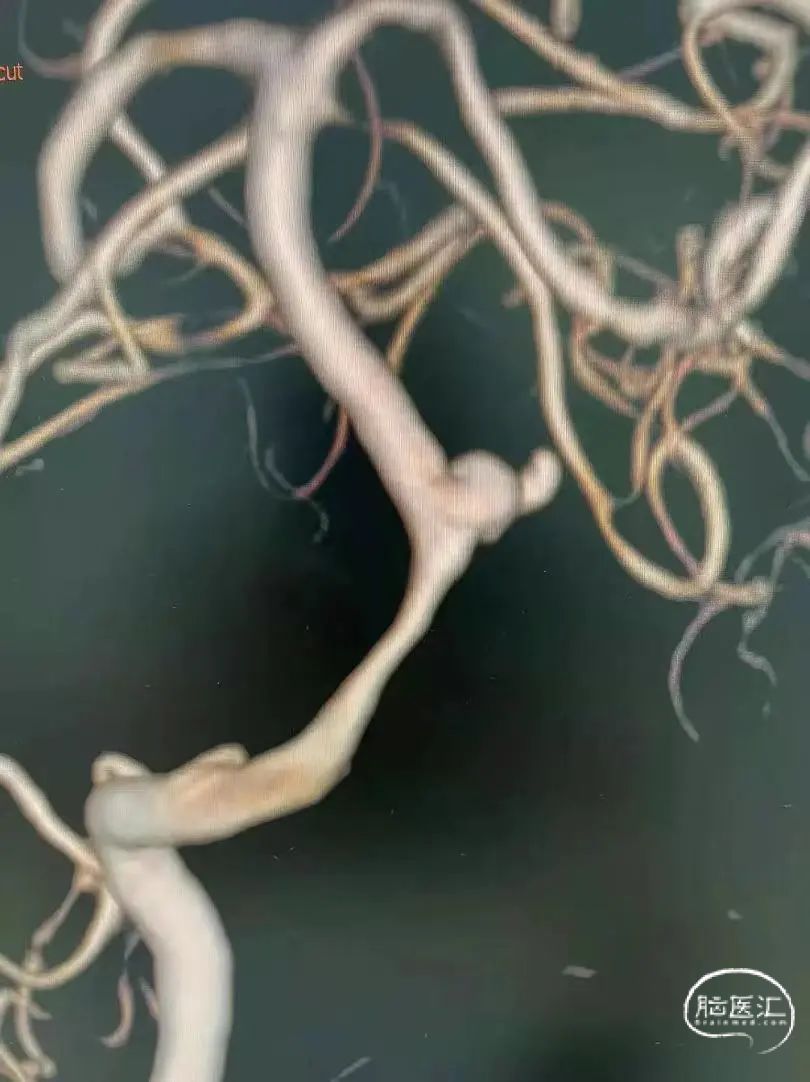

术前影像

栓塞过程

支架半释放先填入两枚弹簧圈,再将支架完全释放,填入四枚Jasper®SS弹簧圈。

本病例为基底动脉中段不规则破裂动脉瘤,采取支架辅助弹簧圈栓塞,Jasper®SS弹簧圈在微导管内推送过程中感觉相对更顺滑,Jasper®SS弹簧圈进入动脉瘤时也能根据其金属的记忆形状自然盘绕顺应性较好。